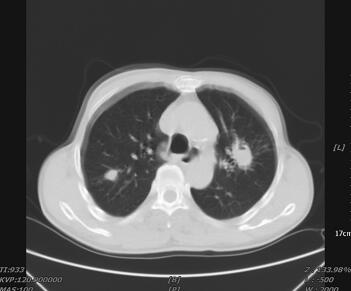

入院第2日(5月25日)22时患者出现胸闷、气喘、端坐呼吸,双肺听诊可闻及广泛湿啰音,中心静脉压18mmHg。B型脑钠肽777pg/ml。床边胸片:两肺纹理明显增多,双肺见多发片状影,密度不均(图2)。考虑出现急性左心衰竭,给予利尿、扩血管降低后负荷、控制输液量与速度,无创通气,症状逐渐缓解。

图2 入院第2日床边胸片示肺部大片状高密度影